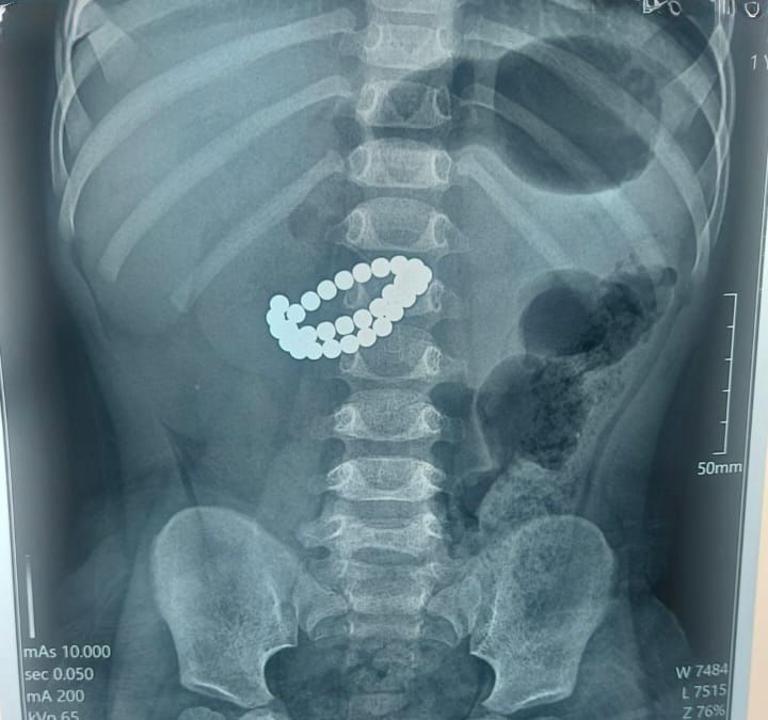

В приемное отделение в крайне тяжелом состоянии поступил малыш в возрасте 1 года 9 месяцев. После обследования врачи установили диагноз: инородные тела кишечника - 31 магнит, множественные перфорации тонкой кишки, диффузный каловый перитонит.

Единственным шансом спасти жизнь ребенка стало срочное хирургическое вмешательство. Медики выполнили срединную лапаротомию с ревизией органов брюшной полости. Хирурги извлекли магниты из кишечника, ушили множественные перфорации тонкой кишки, провели санацию и дренирование брюшной полости, а также трансанальную интубацию кишечника.